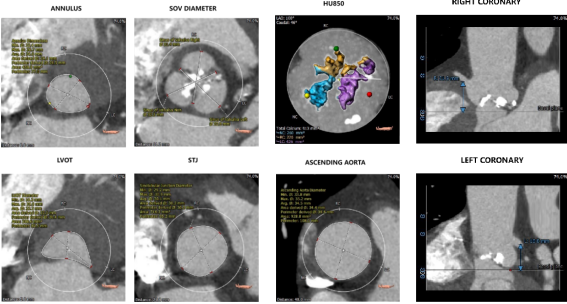

CT数据显示该患者为三叶式主动脉瓣。

1. 主动脉瓣瓣环周长77.0mm,平均周长径24.5mm,SOV:32.6mm*351.4mm*32.2mm,瓣叶增厚,瓣上钙化明显,HU850钙化积分913mm³。

2. 左冠开口高度18.8mm,右冠开口高度21.9mm,高度可,根据瓦氏窦内径和瓣叶长度综合判断,冠脉堵塞风险小。

钙化评估及主动脉根部速览